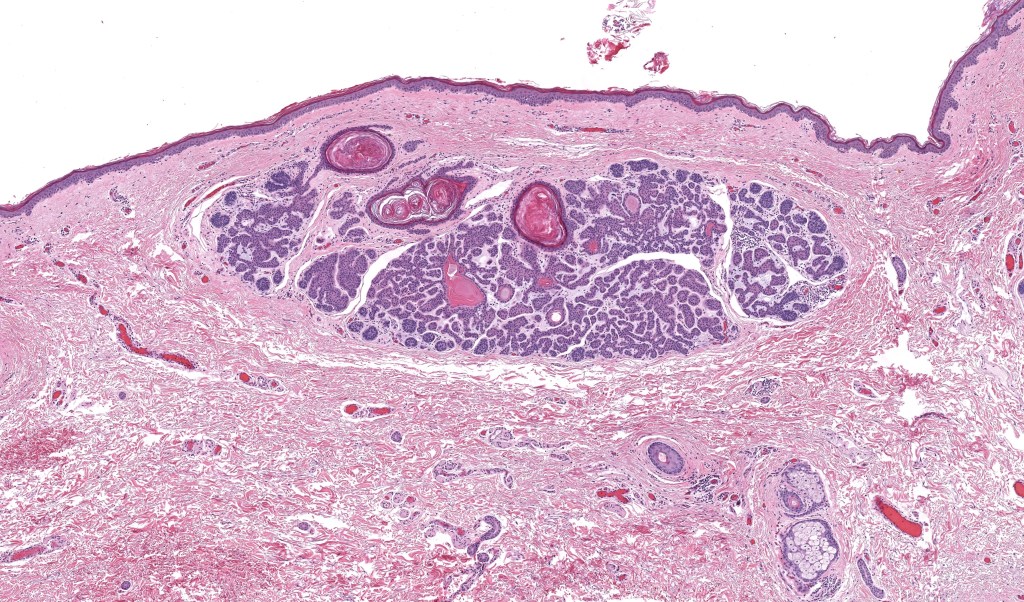

•Vertically orientated, folliculocentric, thin, anastomosing strands composed of basaloid cells embedded in a loose fibrous stroma

•Variable keratocysts

•No retraction artifact or stromal mucin deposition